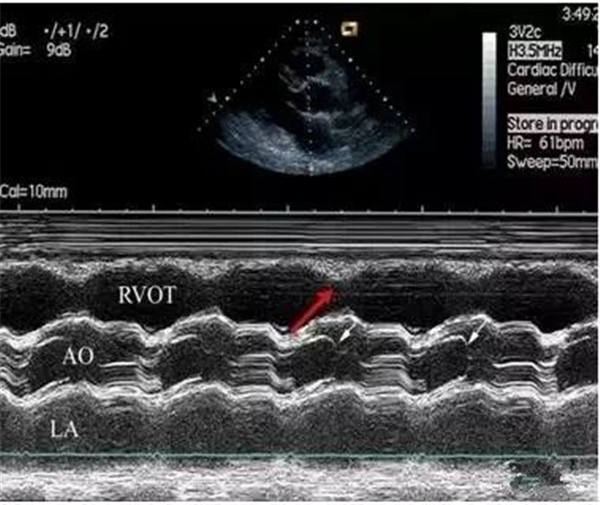

右室壁运动幅度减低

正常情况下,右室前壁运动幅度应>5 mm,右室游离壁运动幅度会>8 mm,但对肺栓塞(PTE)患者,右室壁基底部至游离部运动幅度减低,甚至消失。

幅度降低可视但并非一个量化的标准,因此在把握和判断上存在疑议,这里呢就为大家分享一点观察的要点,同样看图说话:

正常声像图

PTE患者右室壁运动明显减低